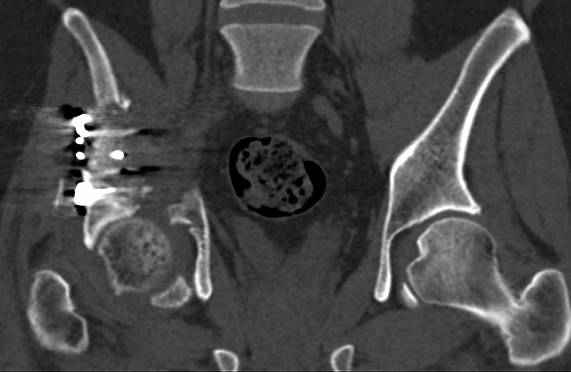

Re: перелом правой половины таза

высылаю дополнительно сканы.